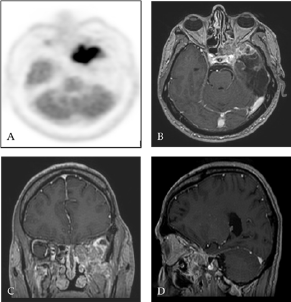

Figure 3: TEP-FDG (A) and contrast-enhanced T1 weighted MRI with gadolinium in axial (B), coronal (C) and sagittal (D) sections ten months after surgery: Presence of an intense hypermetabolic lesion affecting the skull base at the level of the large wing of the sphenoid on the left (ratio of attachment lesion on cortex at 1.7) with contrast-enhancing in the same place.

Ten months after surgery, it was noted the occurrence of ascending epigastric sensations associated with piloerection which occurred 2 to 3 times a day evocative of partial epileptic seizures of the temporal lobe. There was also a numbness in the territory of the left maxillary nerve (V2) with pains in the left temporozygomatic region. A cerebral PET SCAN FDG of end-of-treatment was performed showing a hypermetabolic focus at the skull base in contact with the left temporal operative cavity and cerebral MRI control showed a contrast in the same place in contact with the left wall of the left sphenoidal sinus also invading the round foramen with extension to the left pterygoid muscles (Figure 3).

Endoscopic endonasal biopsy of the spheno-ethmoidal recess was performed and the histological aspect was consistent with recurrence of glioblastoma. At 14 months postoperative the patient had a persistence of some understanding disorders and hypoesthesia at the level of the left V2. On the other hand, there was a rapid visual degradation with a decrease in visual acuity of the left eye. After a multidisciplinary consultation meeting, in view of the rapid visual degradation and taking into account the unmethylated MGMT status, an oncological treatment by targeted therapy of the Avastin type (10 mg / kg or 600 mg / d) with Carboplatin / AUC4 or 630 mg / d combined with 60 Gy radiotherapy delivered in 30 fractions. Sixteen months after surgery the patient remained clinically stable and cerebral MRI control showed a clear regression of the lesion at the base of the skull (Figure 4).

Figure 4: Contrast-enhanced axial T1-weighted MRI 22 months after surgery and medical treatment showing a clear regression of the tumor.